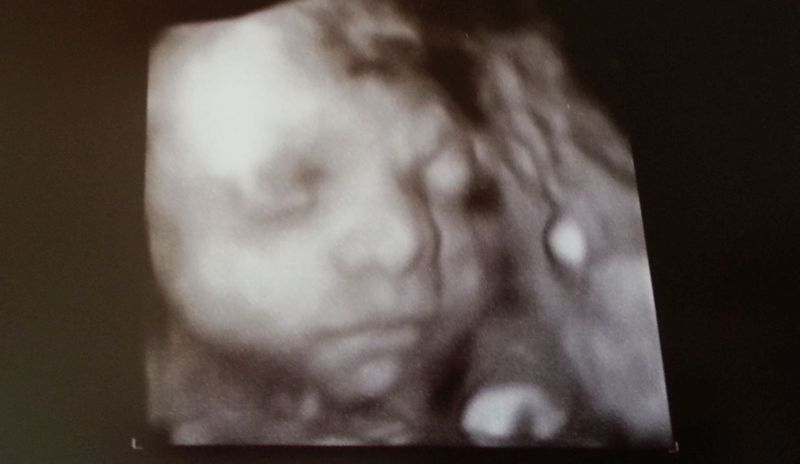

Dlouhé čekání jsem si zpříjemňovala brouzdáním po netu a lovení nových nápadů a inspirací, co mi ještě chybí a čeho naopak mám hodně,… ale když je to tak krásný,…no znáte to. Za chvilku se objevila paní doktorka a šly jsme se kouknout na toho našeho prcka 4D ultrazvukem. Ze začátku se choval jako já. Nerada se fotím, nejsem ten typ, který se dokáže culit do objektivu na požádání a tvářit se jako když mu právě foukly do zadku kilo moučkovýho cukru. Prďola si jednoduše myslel něco o zadní části těla, ksichtík si zakrýval pěstičkami a byl mu vidět jen nos. No a ten mu prý už taky zůstane. No ještě, aby ne. :-O

Po chvíli si dal říct a ukázal se nám v celé své kráse. Párkrát se na nás uculil. Z ultrazvuku si hlavu moc nelámal. Prý vlny, které z něj vychází, miminka většinou ruší a ony se pak snaží co nejrychleji posunout někam, kde na ně nebude nikdo tlačit zvenku a budou mít zase na chvilku klid. A Vašík? Toho jen tak něco nerozhodí, je to pohodář po tatínkovi. Co by se namáhal s nějakým zbytečným pohybem, natož otvíral oči. Spokojeně chrupal, mačkal se a žďuchal mi do břicha, jak se snažil najít tu správnou polohu. Když jsme tedy měly dostatek snímků a paní doktorka mi vypálila celý průběh i na DVD, tak jsem šla zpátky do čekárny a čekal nás zase další odběr.